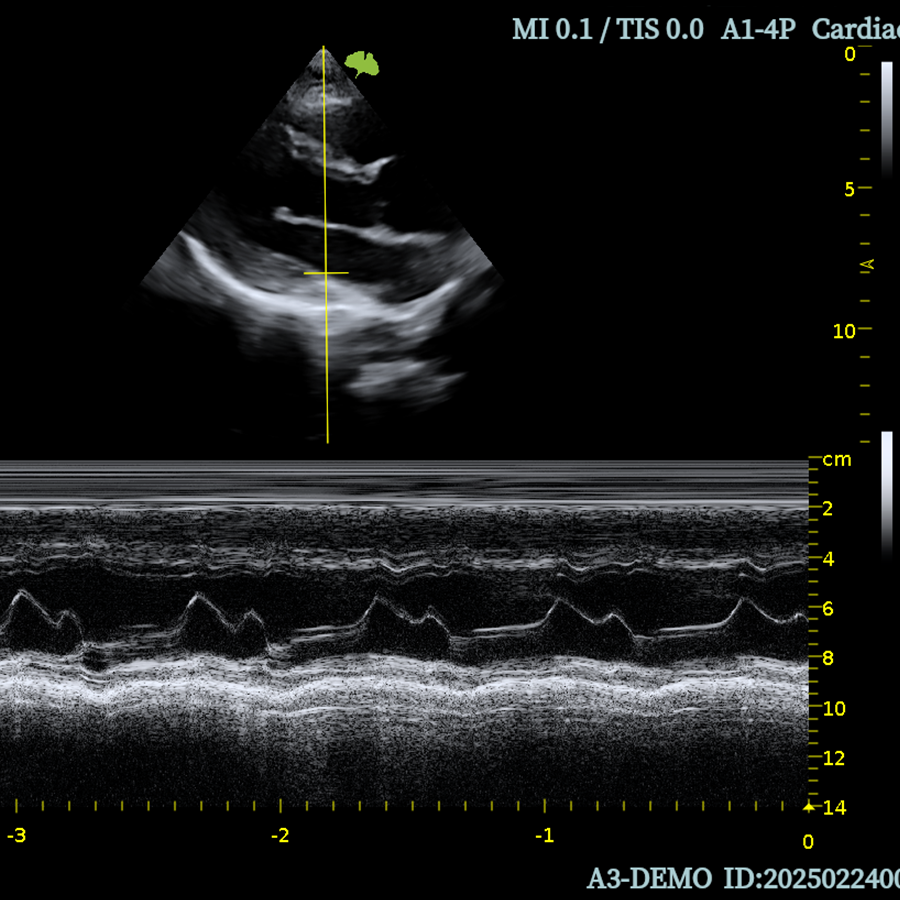

Cardiología

- TD

- M Doppler Color

- MAM

- Auto EF